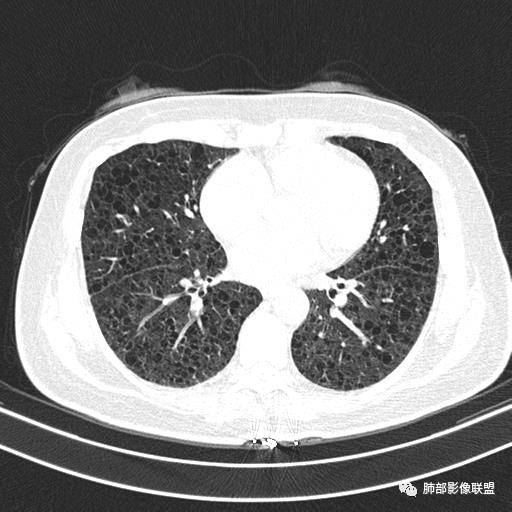

双肺弥漫囊腔,累及肋膈角,囊腔形态相对规则单一。

CT平扫示双肺弥漫分布大小不等囊状薄壁透光区,无内、中、外带分布差异,间质稍示增厚。拟LAM

中年女性育龄期妇女,咳嗽气喘,无吸烟史,有苯吸入史。影像:双肺弥漫均匀小囊腔,无明显分布优势,囊腔形态欠规则,壁薄,部分囊腔边缘血管征,伴双肺弥漫磨玻璃影,无结节,考虑lam,鉴别苯中毒肺损伤,囊腔多有分布优势,小叶中心分布为主,形态规整等

CT表现:双肺弥漫大小不等的薄壁囊腔,囊壁<2mm,外形规则,血管影多位于囊腔周围,囊腔之间肺组织正常,随着疾病进展到晚期,囊腔变大、增多,不可胜数,囊腔可融合成较大的囊,与肺气肿相似,形成间质性肺纤维化。部分病例可出现结节影。